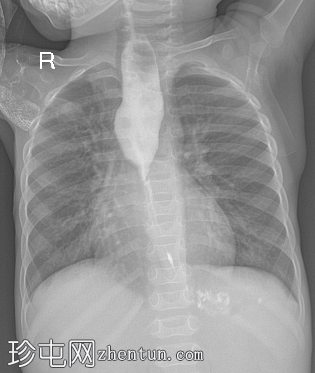

食管造影(正位和侧位)显示近端胸段食管扩张,下段胸段食管呈锥形狭窄,不规则。胃底可见少量造影剂。未见造影剂漏入气道、纵隔、胸膜腔或腹膜腔。